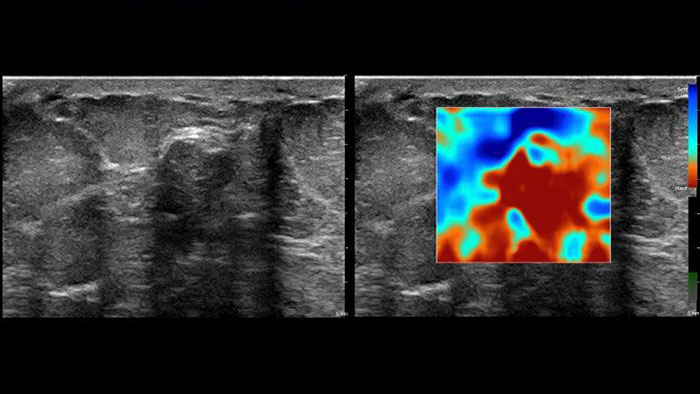

Nowe metody pomiaru sztywności tkanek

Aplikacja US Q-App Elastography Analysis (EA)* pozwala na analizę odkształcenia tkanki na podstawie elastogramu. Można ją stosować w celu porównania rozmiarów dwóch obszarów zainteresowania. Wyniki można dołączyć do dokumentacji pacjenta.

Aplikacja US Q-App Elastography Quantification (EQ)* pozwala na przeprowadzanie oceny ilościowej odkształcenia tkanki na podstawie elastogramu. Użytkownik może wykonywać obliczenia i wyświetlać informacje na temat szybkości odkształcania i odkształcenie całkowite, wyniki porównania rozmiarów dwóch obszarów zainteresowania oraz współczynnik odkształcenia. Dane te można dołączyć do dokumentacji pacjenta.